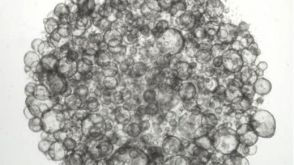

科学海报Human Intestinal Organoid Culture System for Drug-Induced Gastrointestinal Toxicity ScreeningConference:

SOT 2023